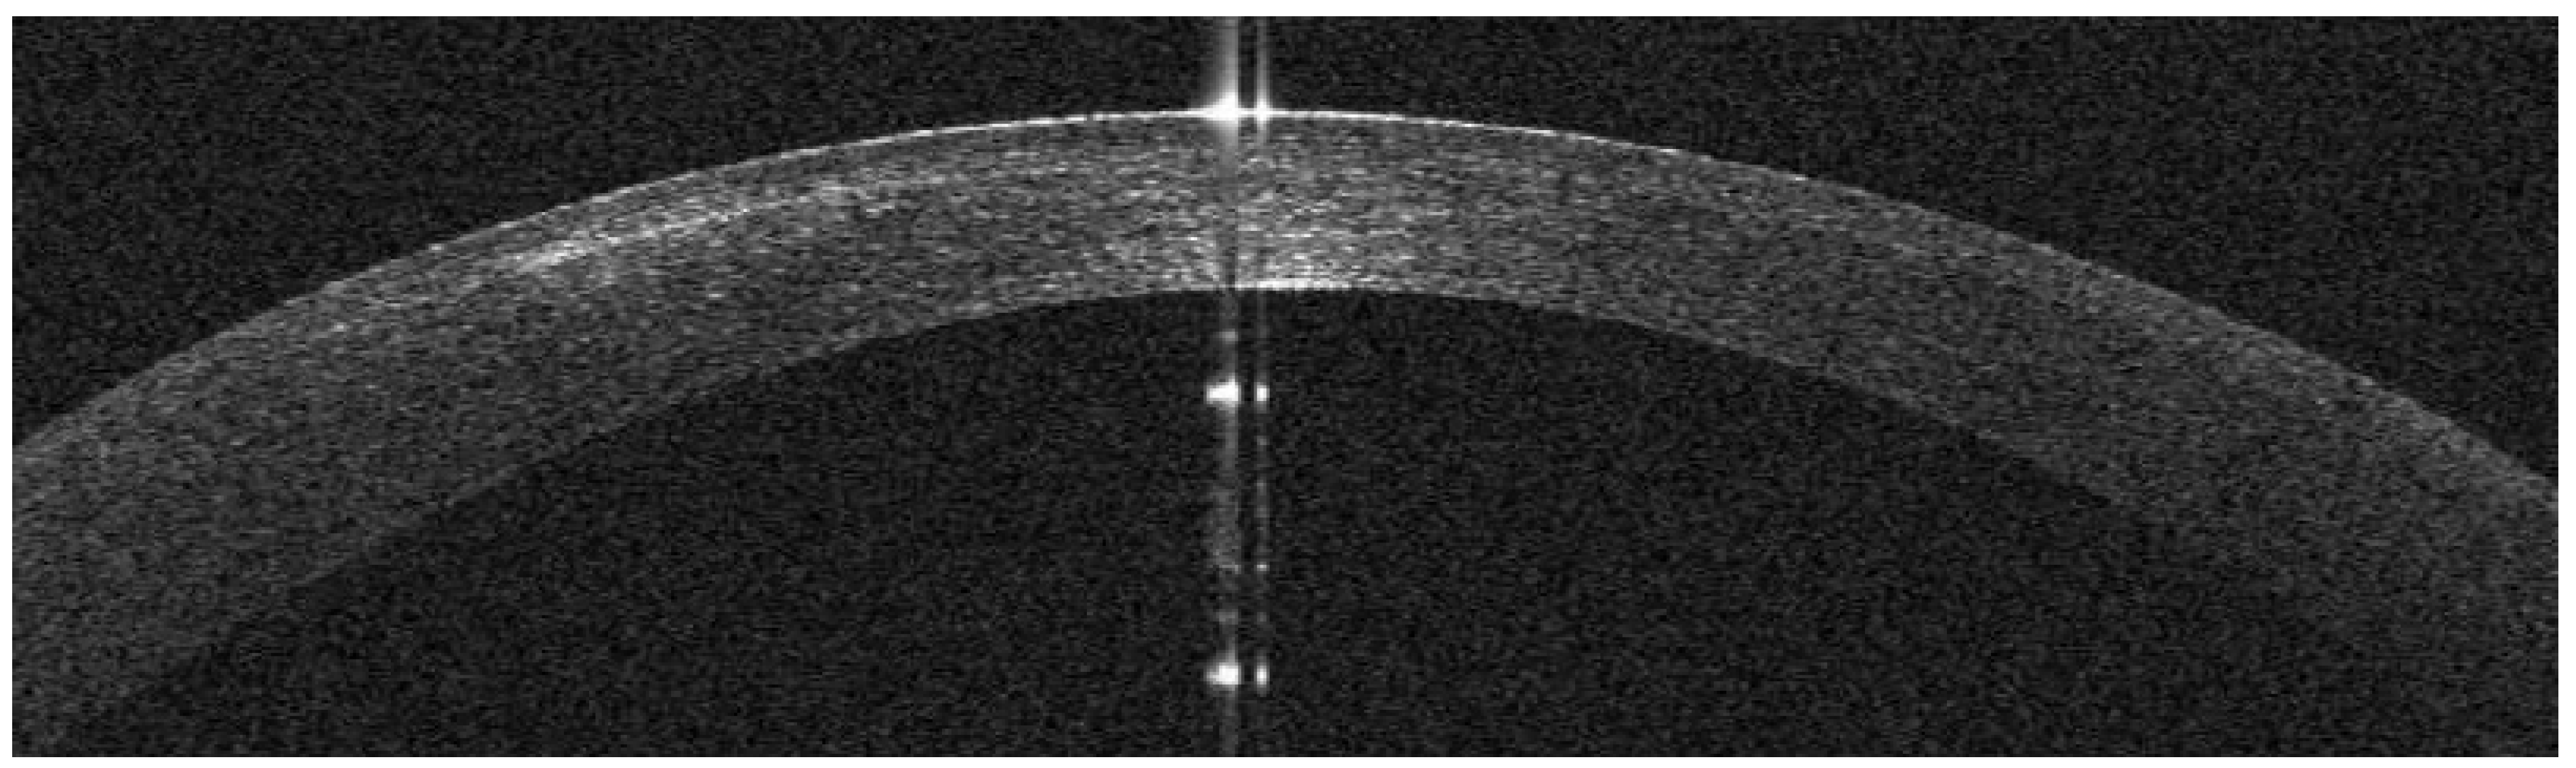

AS-OCT Features